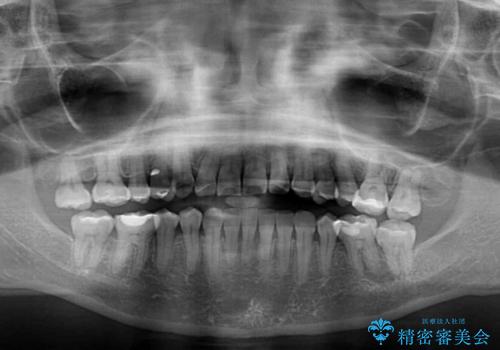

骨格のずれをカムフラージュ クロスバイトのワイヤー矯正

- 骨格的な咬み合わせのズレ、前歯のデコボコとクロスバイトを気にして来院された患者様です。

奥歯の噛みにくさが顕著なためマウスピースではなく、ワイヤー装置による矯正治療を行うこととしました。

下顎の正中を歯1本分ずらした位置とすることで、外見上の骨格的なずれをカバーするように計画しました。

クロスバイトを改善したことで、前歯の負担が軽減し、安定して噛めるようになりました。